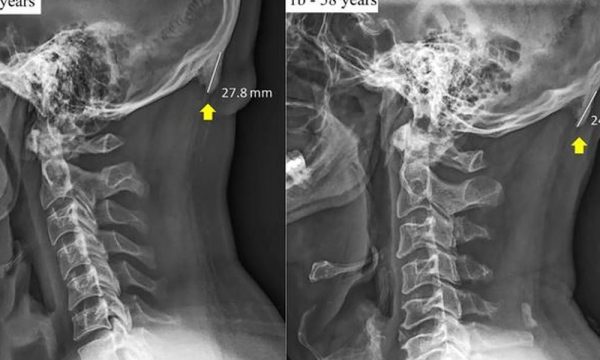

Njerëzit shpenzojnë aq shumë kohë mbi ekranet, e cila ndikon të zhvillohet ‘thumbi kockor’ në pjesën e pasme të kafkës. Studiuesit thanë se është rritur numri i njerëzve që kanë të ashtuquajtur zgjatje...

Një studim i ri tregon se celularët krijojnë disa "thumba" në kocka, të bazuara në kafkë, të cilat quhen zgjatime të zverkut të jashtëm. Ato u konsideruan të rralla kur u diskutuan për herë të parë në...